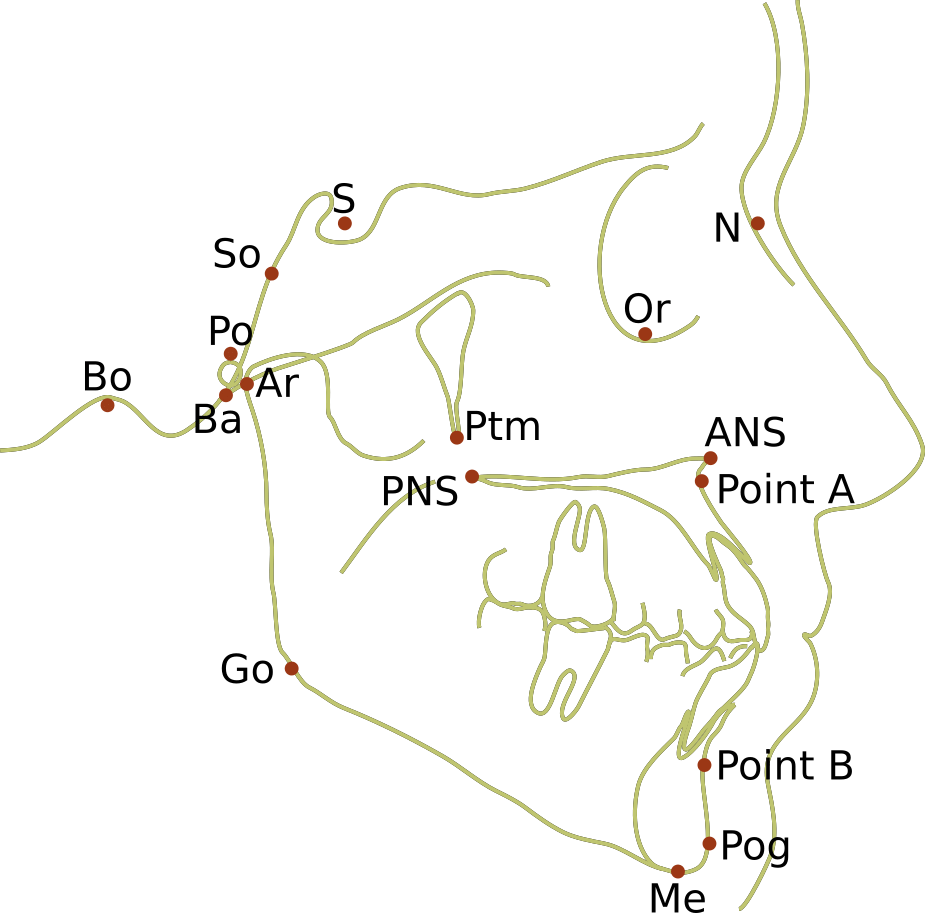

Landmarks for Cephalometric tracing

- Ba – Basion: The most forward and highest point of the anterior margin of foramen magnum.

- Bo – Bolton: The highest point in the concavity behind the occipital condyle.

- Ar – Articulare: The point of intersection of the contour of the posterior cranial base and the posterior contour of the condylar process.

- S – Sella: The midpoint of sella turcica.

- Po – Porion: Outer superior margin of the external auditory canal.

- SO– Spheno-occipital synchondrosis: Junction between the occipital and basisphenoid bones.

- Ptm – Pterygomaxillary fissure: Point at base of fissure where anterior and posterior walls meet.

- Or – Orbitale: Lowest point on the inferior margin of the orbit.

- ANS – Anterior nasal spine: Tip of anterior nasal spine.

- PNS – Posterior nasal spine: The tip of the posterior spine of the palatine bone.

- Point A – Subspinale: Innermost point on contour of the premaxilla between the anterior nasal spine and the incisor tooth.

- Point B – Supramentale: Innermost point on contour of the mandible between incisor tooth and the bony chin.

- Me – Menton: Most inferior point on the mandibular symphysis, the button of the chin.

- Go – Gonion: Lowest most posterior point on the mandible with the teeth in occlusion.

- Pog – Pogonion: Most anterior point of the contour of chin.

- N – Nasion: anterior point of the junction between the nasal and frontal bones.

Cephalometric plane

These are straight lines between two points. There are few you need to know:

- Palatal plane (ANS-PNS).

- S-N plane – represents the anterior cranial base which is often used as a frame of reference for growth because of the early cessation of growth.

- Frankfort horizontal plane/FH plane (P-Or) – habitual horizontal postural position. Often understood as being parallel to the floor. This is regularly used as a reference.

- Functional occlusal plane (FOP) – formed by drawing a line that touches the posterior premolars and molars.

- Mandibular plane (Go-Gn or Go-Me) – connecting the point gonion to gnathion at the inferior border of the mandible.

Angular measurements

The angle measurements are established by using 3 landmarks. For example, SNA is taken by drawing a line from Sella (S), to Nasion (N), to Point A (subspinale), and measuring the angle. Significant variation exists between different races. There are many angular measurements used in orthodontics, but these are likely the ones you need to understand (including what values are normal and what variation will mean clinically).

- SNA – normal 82° ± 2. >84° indicates a prognathic maxilla. <80° indicates a retrognathic maxilla.

- SNB – normal 80° ± 2. > 82° indicates a prognathic mandible. <78° indicates a retrognathic mandible.

- ANB – normal 2° ± 2. This would suggest Class I skeletal relationship. >4° could mean either a retrognathic mandible or prognathic maxilla, and suggests a Class II malocclusion. <0° could either mean a retrognathic maxilla or prognathic mandible, and suggests a Class III malocclusion.

- Mandibular plane angle – Gonion to menton is the mandibular plane. It can be visualized externally by placing a straight object on the inferior border of the mandible. When compared to S-N (MP-SN), it gives you the mandibular plane angle. Normal is 14°. >14° suggests a vertical growth pattern with a long lower face and a tendency to Class II. <14° suggests a flat growth pattern with a short face and a tendency towards Class III.

- Maxillary Mandibular Plane Angle (MMPA) – the angle between the mandibular plane and the maxillary plane (ANS to PNS line). Normal value 27° ± 4. The greater the MMPA, the longer the anterior facial height and tendency to Class II. The smaller the MMPA, the shorter the facial height and tendency to Class III.

- Y-axis – S-N to S-Gn: a larger angle indicates more vertical development, long face and anterior open bite tendency.

- 1/-FH – Upper incisor angulation in relation to the Frankfort horizontal plane, usually 60°. A smaller angle indicates flared incisors.

- /1-MP – Lower incisor angulation in relation to the cranial base, usually 90-100°. A large angle indicates flared incisors.

- 1/-/1 – Interincisal angle, average value 130°.